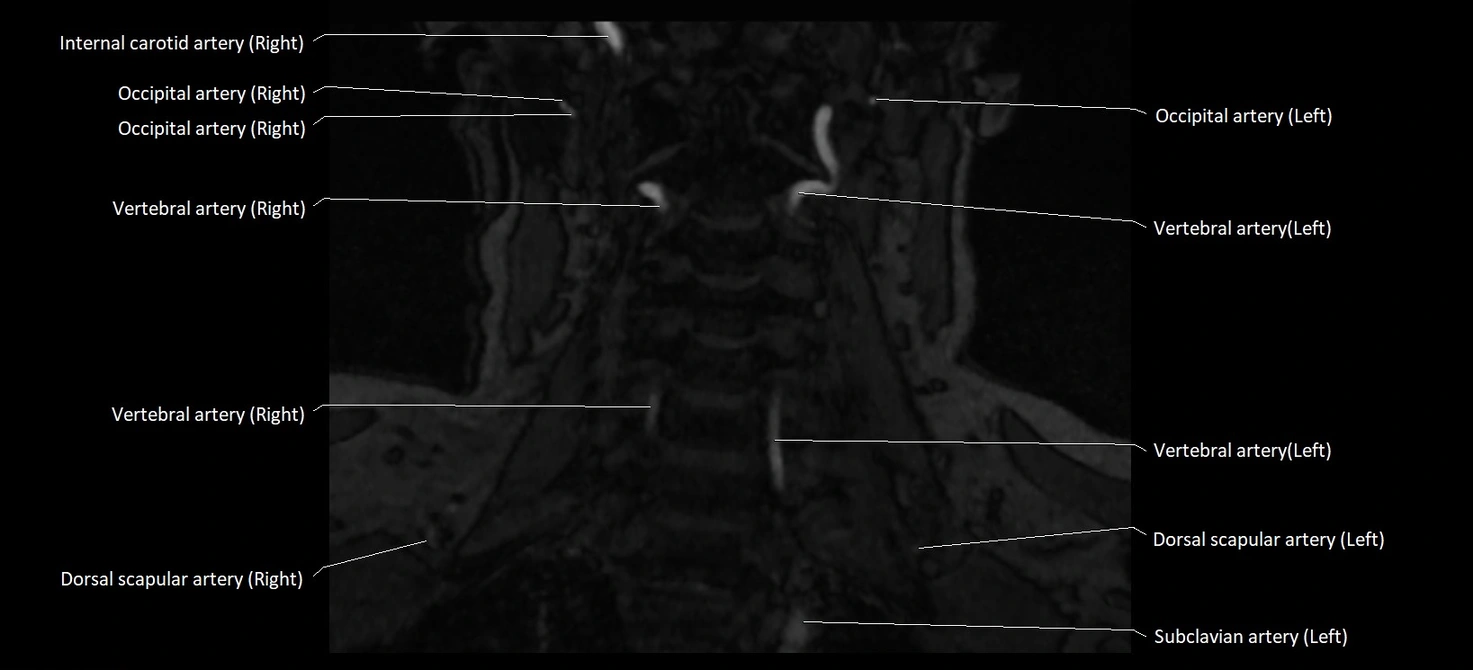

MRI images

image